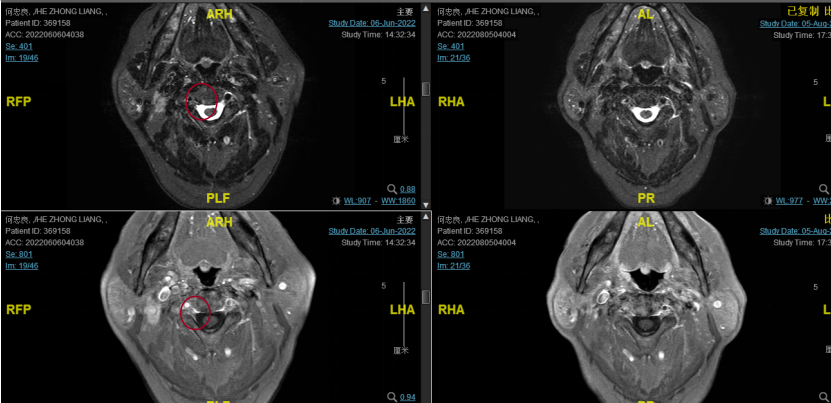

2022-08-05(放疗近结束)复查MR,疗效评价:CR。鼻咽部肿物及咽后转移淋巴结颈部转移淋巴结均达到CR。

按照传统鼻咽癌治疗模式,约80%的患者可以获得很好的长期生存,但是还有20%的鼻咽癌高危人群会出现复发转移,而这部分患者主要包括T3、T4及N2、N3局部晚期及EB病毒拷贝数非常高或治疗后EB病毒拷贝数不能恢复到0的患者。该患者初诊时为T4N3Mx,局部分期较晚,诱导治疗期使用了斯鲁利单抗联合尼妥珠单抗、化疗治疗2周期,病灶较前缩小。后予放疗同步斯鲁利单抗、尼妥珠单抗、恩度治疗,所有病灶均达到了CR,避免了手术带来的损伤。